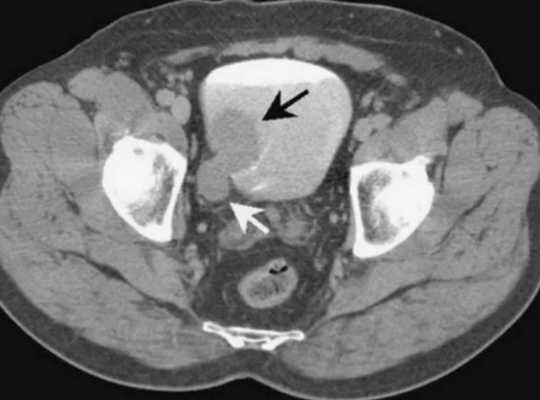

Опухоли мочевого пузыря

Визуализируется экзофитно растущее в просвет мочевого пузыря объемное образование на ножке (папиллярная уротелиальная опухоль).

С целью оценки глубины инвазии опухоли в стенку мочевого пузыря при МРТ исследовании используется внутривенное динамическое контрастирование.

Неинвазивная папиллярная уротелиальная опухоль. Корональное Т2-взвешенное МР- изображение показывает тканевой интенсивности сигнала опухоль (стрелка),растущая в просвет мочевой\го пузыря. При бесконтрастном исследовании создается впечатление о сохранности прилежащих отделов гипоинтенсивной стенки мочевого пузыря. Однако достоверно судить о степени глубины инвазии можно только по постконтрастным сканам.

При этом важно проведение именно динамического внутривенного контрастирования (в артериальную фазу происходит усиление только ткани опухоли, но еще не успевает произойти усиление интактной стенки мочевого пузыря). На представленном контрастном Т1-ВИ изображении (артериальная фаза) на фоне накопления КВ тканью опухоли, подслизистого слоя, видно отсутствие инвазии прилежащей стенки мочевого пузыря.